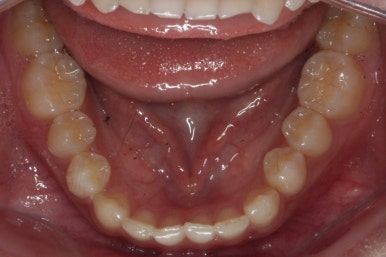

위 사진들은 부산매복치아교정 키다리아저씨치과에 처음 내원하셨을 때의 모습입니다.

화살표 표시한 부분이 바로 영구치 송곳니가 있어야 할 자리인데, 매복이 되어있고 대신 유치가 여전히 남아있는 모습입니다.

아래치아는 여전히, 당연히 장치가 붙지 않은 채로 그대로 둡니다.

썩은 유치 대신 영구치 송곳니는 매우 자연스럽게 위치되었습니다. 아랫니는 교정하지 않았기 때문에 약간 삐뚠 느낌은 남아있지만 맞물림은 크게 문제가 없게 마무리 되었습니다.